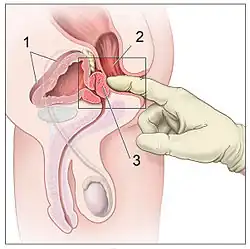

Le CTMH préconise d'effectuer, en plus de l'interrogatoire, un score symptomatique du type de l'International Prostate Symptom Score (IPSS) ainsi qu'un examen physique comprenant en bilan de première intention :

- un toucher rectal (palpation de la prostate à travers le rectum) qui permet d'en apprécier la taille et de détecter une irrégularité qui peut être le premier signe d'un cancer ;